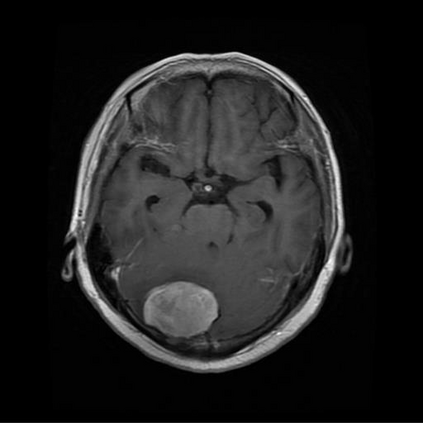

Deep learning algorithms have accounted for the rapid acceleration of research in artificial intelligence in medical image analysis, interpretation, and segmentation with many potential applications across various sub disciplines in medicine. However, only limited number of research which investigates these application scenarios, are deployed into the clinical sector for the evaluation of the real requirement and the practical challenges of the model deployment. In this research, a deep convolutional neural network (CNN) based classification network and Faster RCNN based localization network were developed for brain tumor MR image classification and tumor localization. A typical edge detection algorithm called Prewitt was used for tumor segmentation task, based on the output of the tumor localization. Overall performance of the proposed tumor segmentation architecture, was analyzed using objective quality parameters including Accuracy, Boundary Displacement Error (BDE), Dice score and confidence interval. A subjective quality assessment of the model was conducted based on the Double Stimulus Impairment Scale (DSIS) protocol using the input of medical expertise. It was observed that the confidence level of our segmented output was in a similar range to that of experts. Also, the Neurologists have rated the output of our model as highly accurate segmentation.